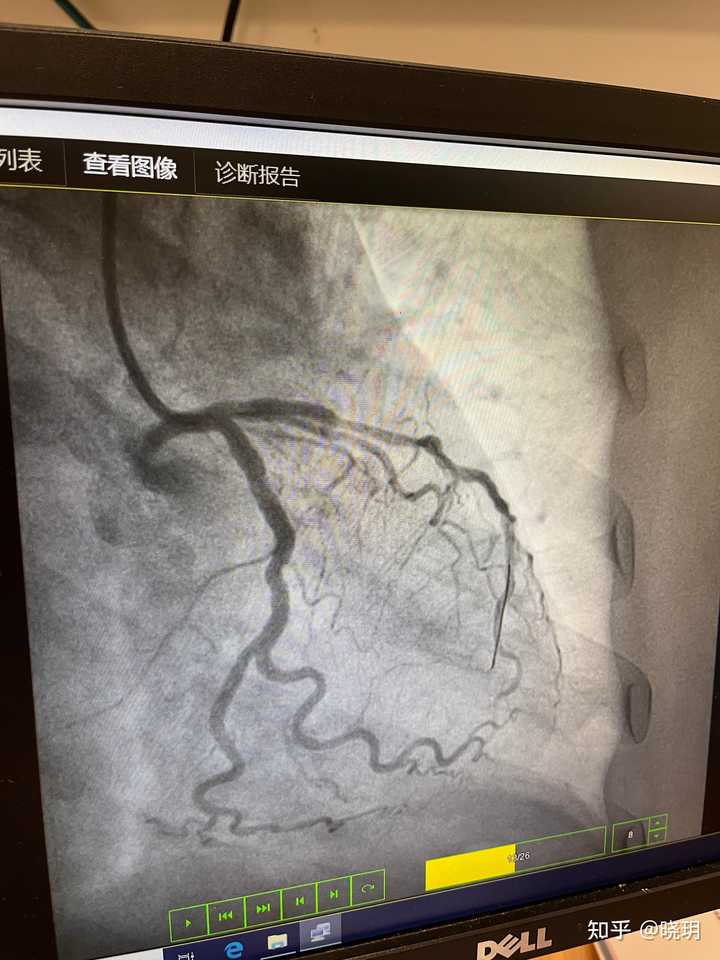

医院不让拍照,我就放一张照片吧

是前降支,xx支,xx支。其中一根堵99%下了1个支架,另外2根堵60-70%,不做处理。

造影堵了三根血管,其中主动脉堵了99%,两根支动脉堵了70%,也没等我媳妇儿来签字就直接下了一个支架。